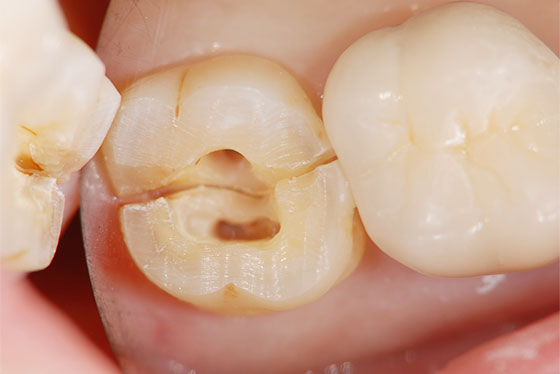

歯の上部が割れた場合と、歯の根が割れた場合とでは、治療法や治療の難易度が異なります。「歯の上部」が割れた場合は、基本的に抜歯せずに治療が可能です。しかし、「歯の根」が割れた場合、多くのケースは抜歯の選択となります。

しかし、「歯の根」が割れた場合でも、一度、その歯を意図的に抜歯し、割れた部分を処置して再度元に戻す「意図的再植術」を行うことで最終的には抜歯せずに治療ができることもあります。

以下、他院で「抜歯」と言われた歯を残したケースになります。

他院で「歯の根が割れてるので、抜歯になります」と言われた場合でも、実際は割れておらず、通常の根管治療で対応ができる場合があります。